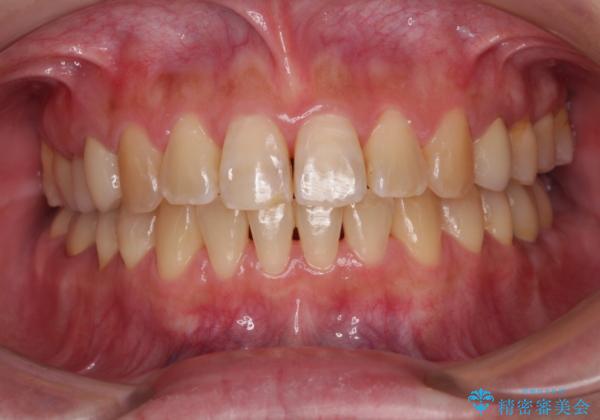

開咬により奥歯のみが接触している状態で、前歯部にほとんど接触のない状態で、奥歯に非常に負担のかかる咬み合わせでした。

まずはむし歯の治療を行い、その後ワイヤー矯正にて咬み合わせを改善し、途中インプラント埋入を行い、矯正治療後に補綴治療を行うこととしました。